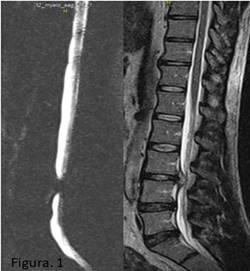

Se realizaron estudios de la columna lumbo sacra por imagen de resonancia magnética (IRM) que arrojó la presencia de una lesión isointensa que ocupaba el diámetro del canal a nivel de la cuarta vértebra lumbar (L4), que se correspondía con ese espacio intervertebral y producía una parada del contraste mielográfico a ese nivel (Figura 1).